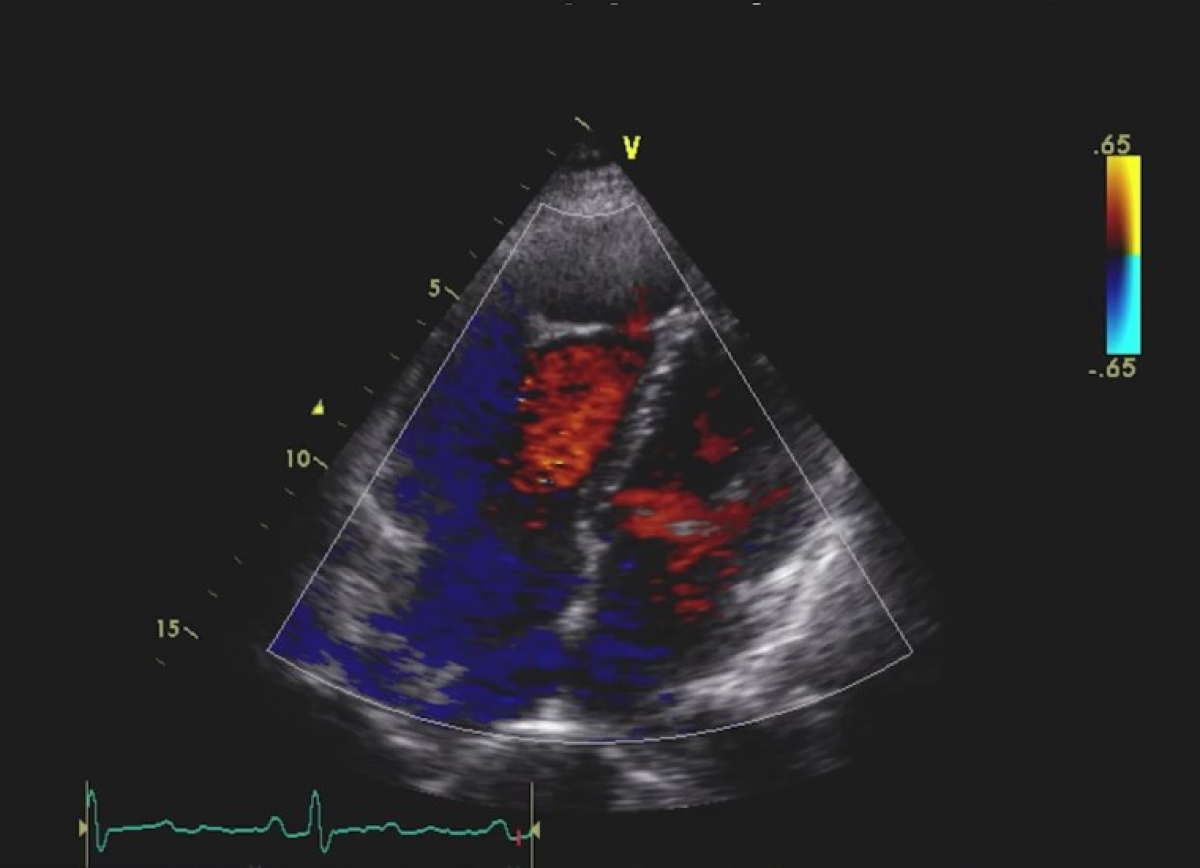

Pacjent z narastająca dusznością z podejrzeniem niedomykalności aortalnej.

Przewlekłe rozwarstwienie aorty z ciężką niedomykalnością aortalną.

Echokardiografia przezklatkowa i przezprzełykowa.

Echokardiografia trójwymiarowa.

Ocena niedomykalności aortalnej.

Diagnostyka rozwarstwienia aorty.